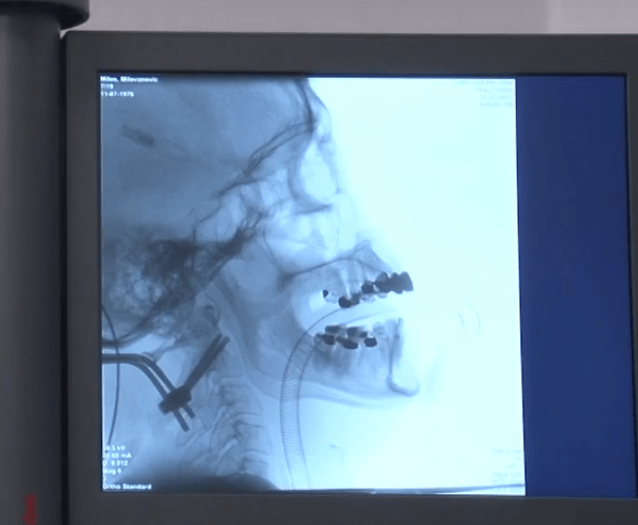

“During the first operation we have done fixation from occipital bone to second cervical vertebrae. The second one was performed from the anterior part of the neck, with special screws that passed through the base of the vertebrae up to broken part in order to close it to the base and to make contact – bone to bone. That is a guarantee for a definitive fixation of the fracture and complete healing”, says dr Savić and explains that in case that patient had come immediately after the accident, it would have been needed only the anterior operation.

“Special surgical cutting edge screws that were designed exclusively for the neck were used and are very modern. It is required to have surgical knowledge and demanding technical conditions- that is the reason why such operations are not performed in other hospitals. In this hospital (Atlas Hospital) we have succeeded to perform these operations completely successfully and with safety, says dr Savić.